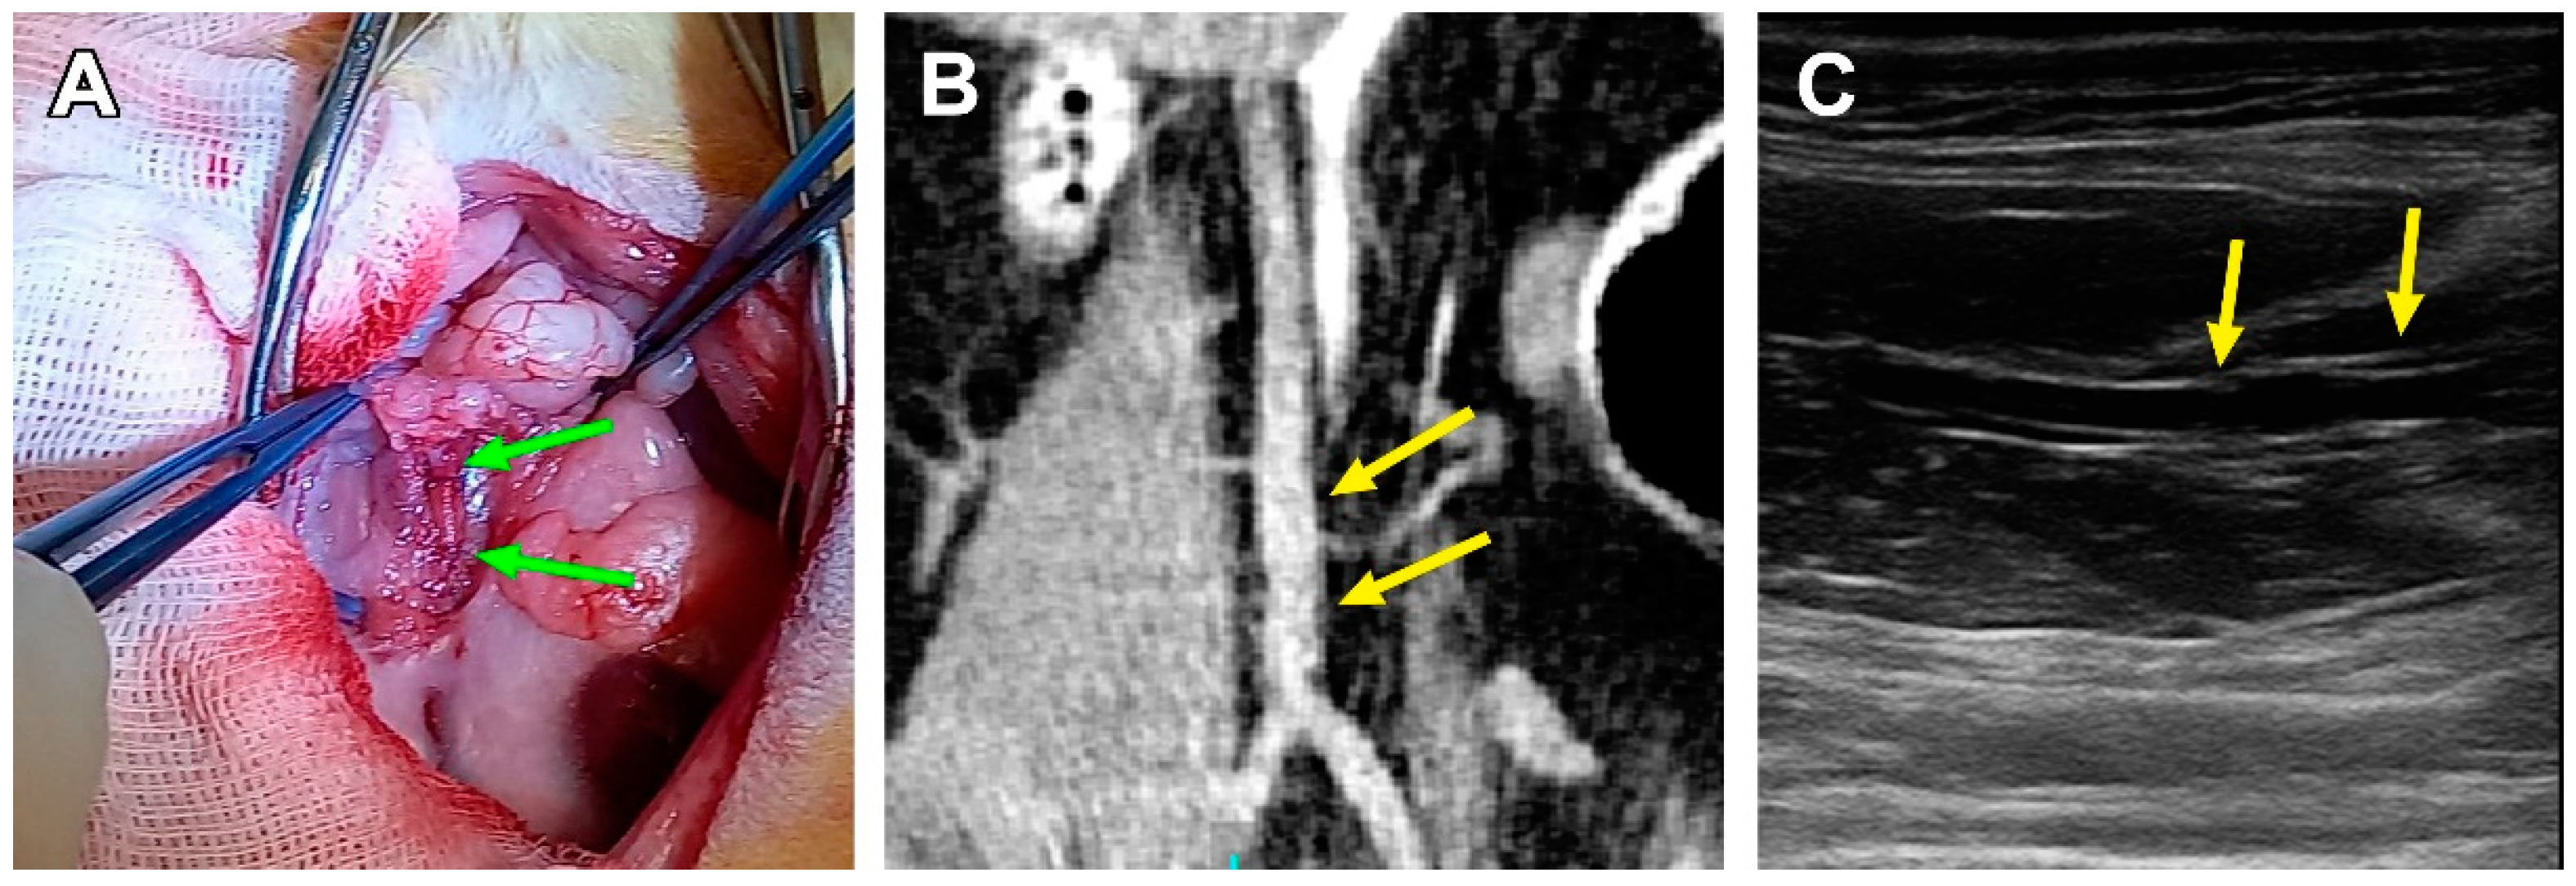

2.6. Angiography

2.7. Ultrasound Diagnostics

3.2. Surgical Outcomes

3.3. PCL Scaffold Transformation